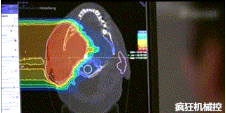

▲360°重離子治療一體機(jī)治療腫瘤

360°重離子治療一體可從任何角度用重離子(碳,氦,氧)和質(zhì)子(氫)照射腫瘤。此外,基于機(jī)器人的治療臺(tái)可以通過(guò)六種方式進(jìn)行調(diào)整。

光柵掃描被集成到360°重離子治療一體機(jī)中,這種極其精確的照射方法以毫米為單位掃描腫瘤,可以保護(hù)健康組織且只治療腫瘤區(qū)域。

特別是腫瘤在高度輻射敏感位置或者諸如視神經(jīng)附近的復(fù)雜位置,可以通過(guò)選擇最佳射束入射角來(lái)減小這些器官的損傷。